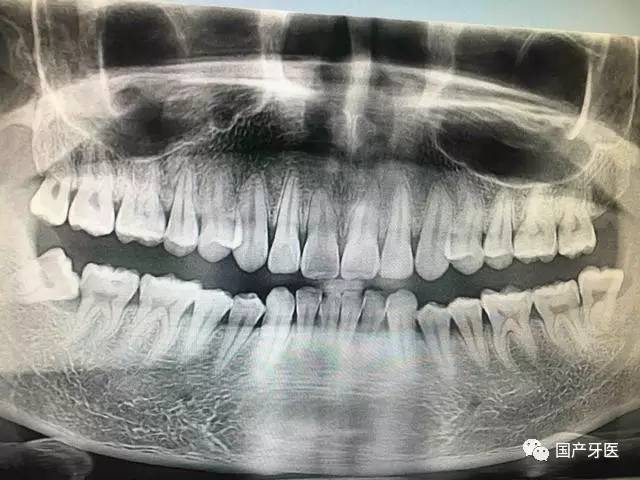

本人全口X片,四颗智齿,左下最后一颗近中阻生

拔除智齿只是缺了一颗牙齿,颌骨长度、宽度都没有改变,谈何瘦脸呢?我不知道这些谣言都是从哪传出来的。